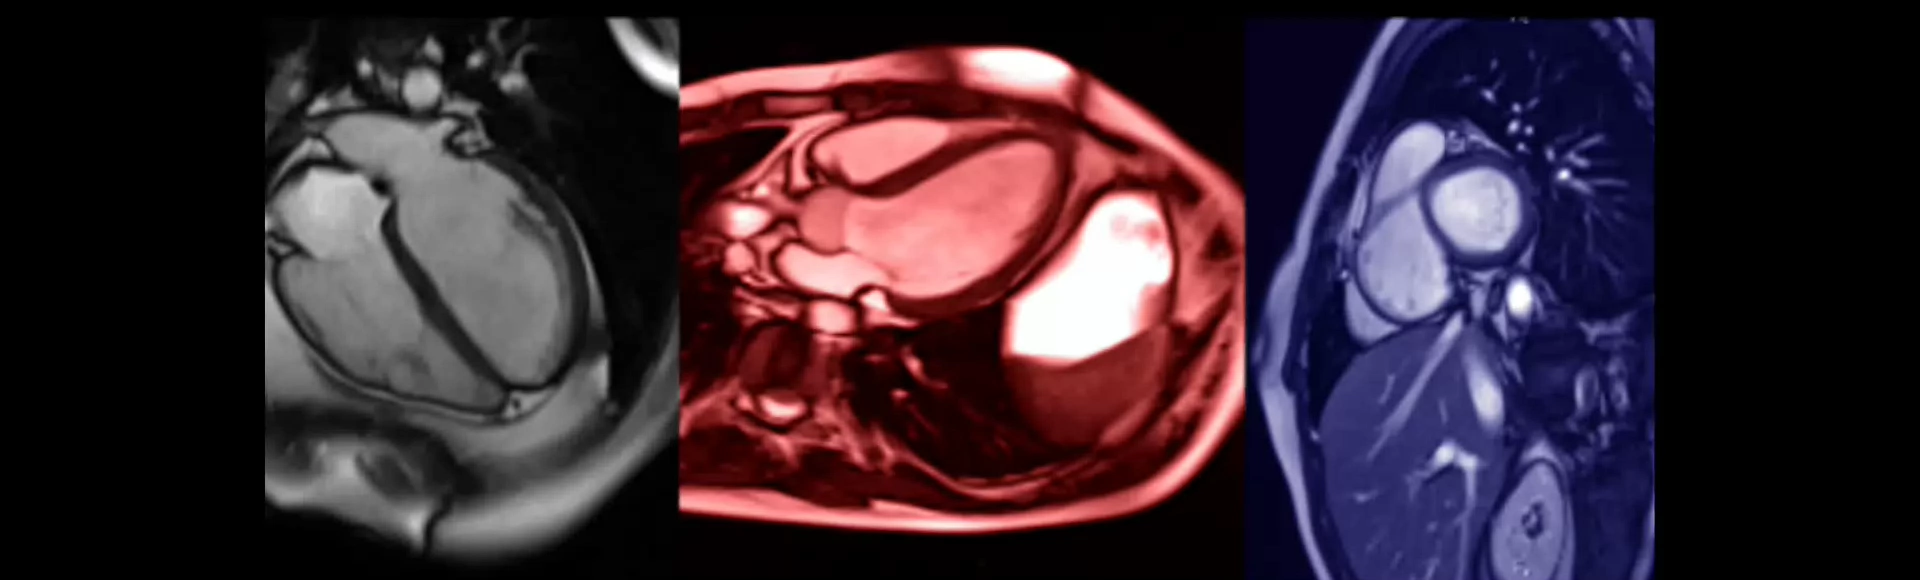

Bij het scannen van het hart op een MRI scanner worden veel verschillende technieken en sequenties gebruikt. Al deze technieken en sequenties hebben hun eigen parameters die aangepast moeten worden voor het optimaal afbeelden van het hart.

De nadruk bij deze cursus is het begrijpen en optimaliseren van deze technieken en sequenties en het aanpassen hiervan bij verschillende hartfrequenties.

Deze cursus is opgedeeld in 4 modules waarbij in module 1 het elektrocardiogram (ECG) triggeren en functionele opnames uitgebreid aan bod komt. In module 2 worden de specifieke cardiac sequenties behandeld en module 3 staat in het teken van flow-kwantificatie. In module 4 worden aan de hand van casuïstiek uit de praktijk alle technieken, onderzoeksmethodes en gebruikte pulssequenties nogmaals besproken.